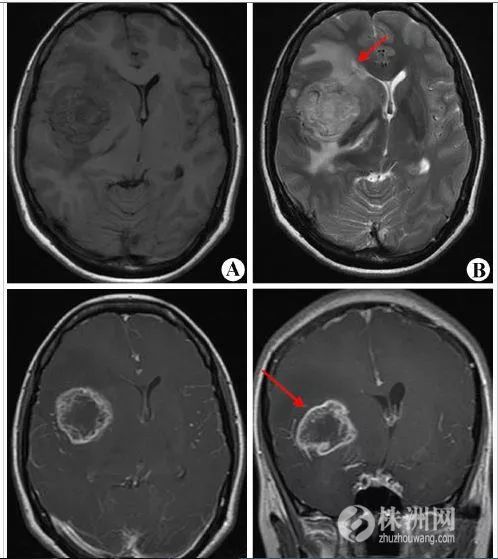

近来,关于使用手机超过10年可能使人更容易患脑瘤的新闻引起了网友的热议。

那么,真相到底是怎样的呢?手机打多了会不会导致患脑瘤的风险增加呢?今天,我们就来科普一下。

手机和脑瘤的关系

关于手机和脑瘤的关系,由于缺乏长期前瞻性队列研究这样强有力证明因果关系的数据,目前还是定性为“可疑致癌因素”,所以不必过分紧张。然而不少研究也发现了两者之间的相关性,因此也不能掉以轻心,特别是常年大量使用手机的用户以及20岁以下的年轻人及少年儿童。